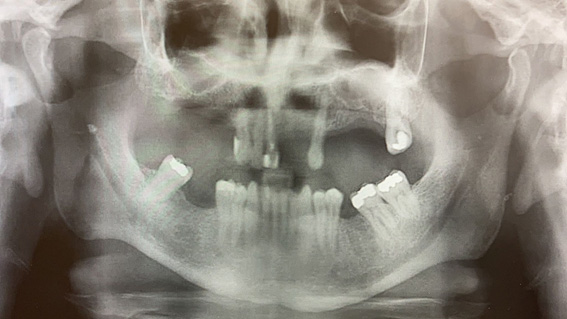

Se solicita una ortopantomografía y se dan pautas a seguir para mejorar sintomatología, insistiendo en beber abundante agua y tomar antiinflamatorios en caso de dolor. Tras valorar la Ortopantomografía observamos un sialolito en zona derecha procedente de la glándula parótida. En la zona izquierda puede observarse también otro cálculo de menor tamaño.  El tratamiento en este caso será encaminado en la eliminación del cálculo. Al no observarse en la salida del conducto con la técnica bimanual se decide realizar derivación al servicio de cirugía maxilofacial del hospital de referencia en el cual será tratado. CONCLUSIÓN